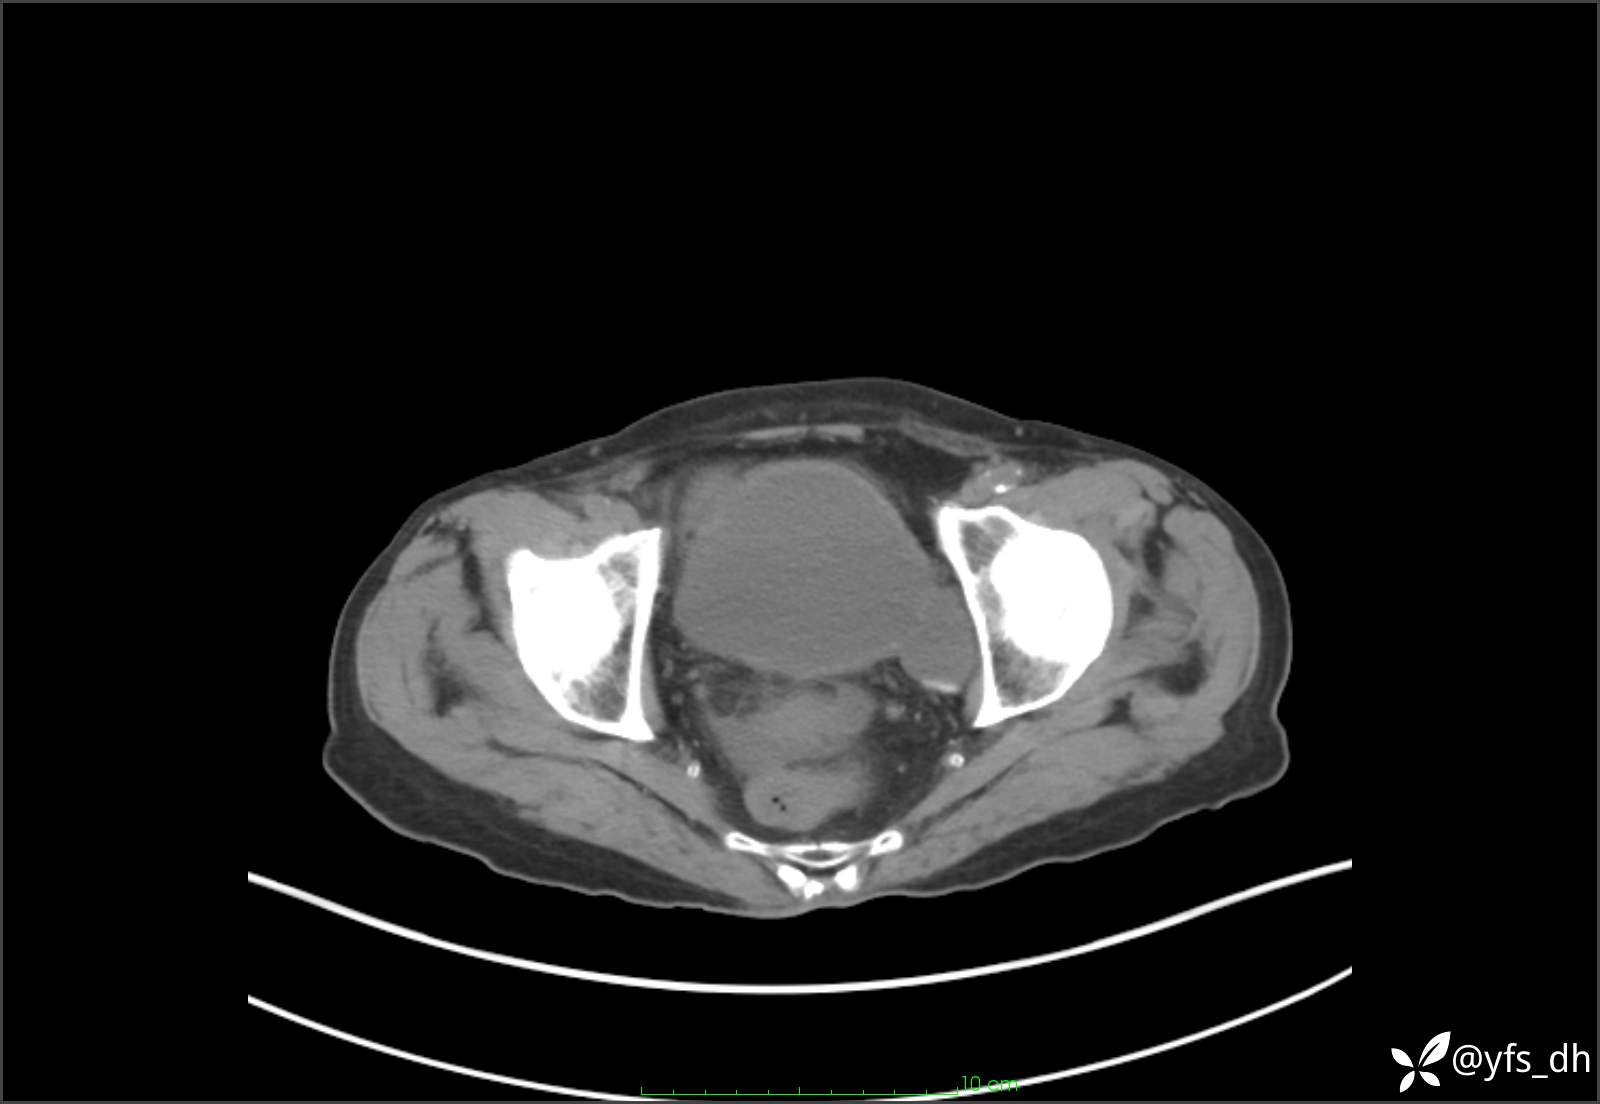

1.简要病史:患者4天前突发上腹部疼痛不适,但可以忍受。3小时前饭后突然加重,不能忍受后就诊。

2.简要手术记录:术中见腹盆腔大量肠液及粪便,乙状结肠中下段见一约3cm的破口。